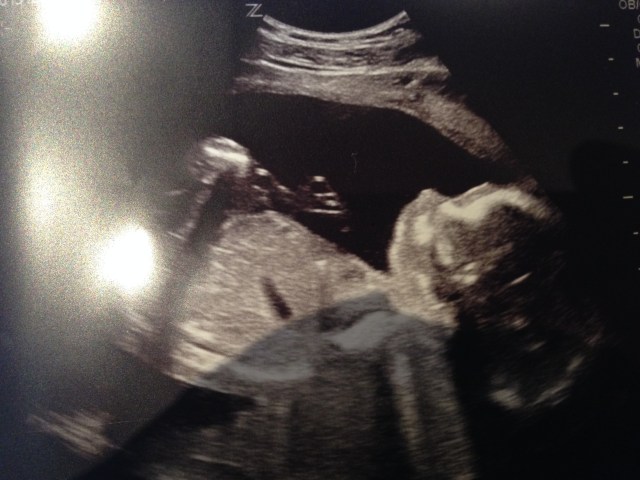

Men best av alt, ja, det var beskjeden jeg fikk i går. Da var jeg på ordinær ultralyd – endelig – og gjett hva. Jeg ble satt en hel uke frem! Lykken i livet for en som ble satt en uke tilbake sist gang, og i tillegg gikk langt over tiden 🙂

Neida, neida, slapp av. Det var selvfølgelig ikke det som var det beste med den ultralyden, selv om jeg innrømmer at det hjalp på humøret. For der inne ligger det en frisk, rask og veldig aktiv lillebror. Tenk på det da – for et lite (stort) under!

La meg introdusere: bittelille bøllebror!